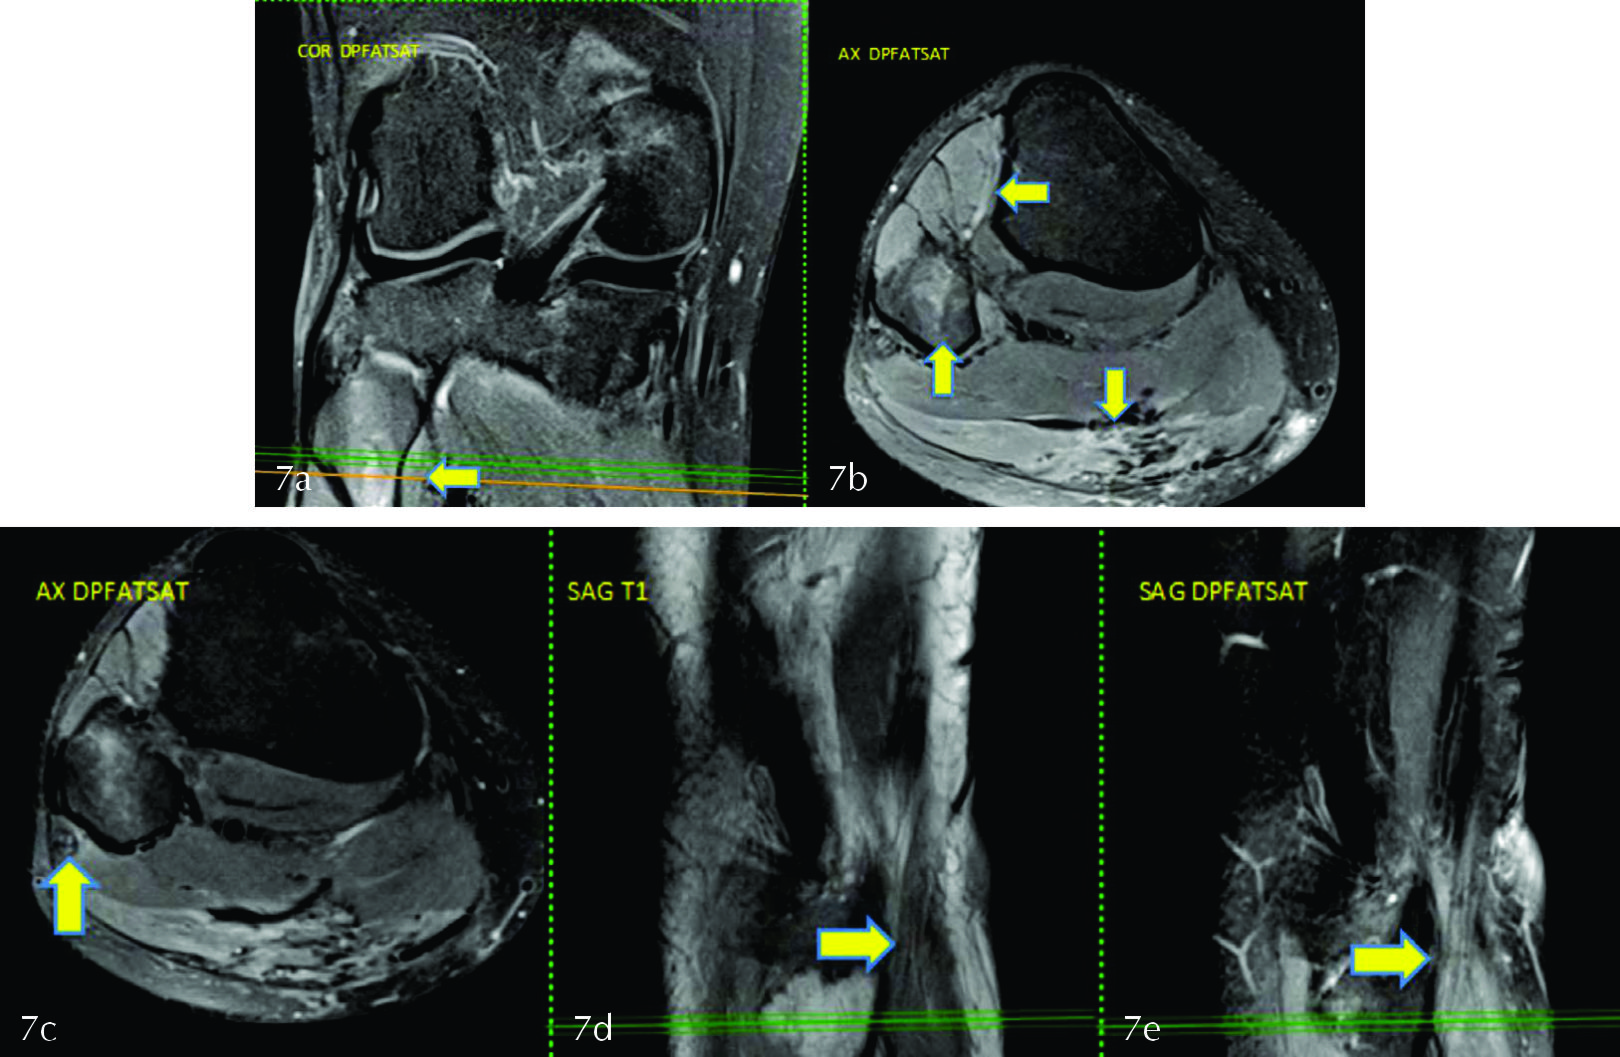

Paciente de 41 años, SM, que consulta por traumatismo de codo. Se solicita RM de codo y antebrazo que muestra aumento de señal en DPFATSAT con características de edema muscular en el flexor profundo de los dedos y flexor ulnar del carpo, ambos territorio del nervio cubital (fig. 2 a, flechas rojas). No se evidencia atrofia muscular en T1 (fig. 2 b). Este patrón de denervación orienta a lesión del nervio cubital identificándose sección del mismo en los cortes a nivel del codo, con pérdida de su patrón fibrilar normal en T1 e hiperintensidad en DP FAT SAT (fig. 2 c,d,e). La neuropatía del nervio cubital es la segunda en frecuencia en el miembro superior y el túnel cubital es el sitio mas frecuente de lesión o compresión del mismo(6). Puede ser de causa traumática como en nuestro caso o compresiva, por luxación del nervio, ancóneo epitroclear, quistes u osteofitos, entre otros (2,6).

En nuestro paciente se evidenció edema en el músculo extensor de los dedos (flecha celeste en 2 a), territorio del nervio radial. Dada la afectación aislada de un músculo de su territorio no orienta a lesión del nervio sino que puede estar en relación a contusión muscular por traumatismo directo.

Figura 2

Imágenes axiales de antebrazo donde se evidencia edema de los planos musculares flexores (flechas rojas en a) y en el extensor de los dedos (flecha celeste en a). Imágenes axiales a nivel del codo donde se visualiza el nervio cubital engrosado, con aumento focal de la señal en la secuencia DP FAT SAT (flecha en c) y perdida del patrón fibrilar normal en T1 (flecha en d). En el plano sagital se observa sección del nervio cubital (flecha en e).